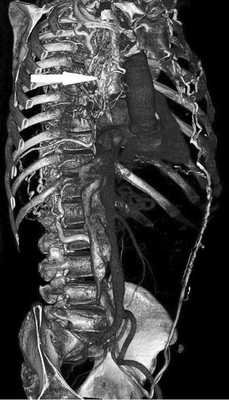

По данным компьютерной томографии (КТ), в ПП обнаружено дополнительное образование дольчатого строения, с полицикличными ровными контурами, довольно однородной структуры, занимавшее всю полость ПП и пролабирующее в полость ПЖ на ½ его объема. Размеры образования 5,9×7,5×8 см. Выраженный венозный коллатеральный кровоток. Полые вены без дефектов наполнения (тромбов) в просвете (рис. 2).

Рис. 2. Рентгеновская компьютерная томография с контрастным усилением в 3D-реконструкции (Siemens SOMATOM Sensation 64). Стрелкой обозначена коллатеральная сеть венозного возврата в системе верхней и нижней полой вен, развившаяся в связи с обструкцией правого предсердия.